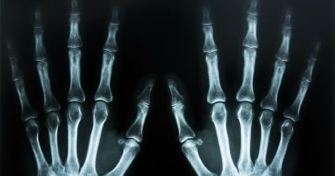

Röntgen: So funktioniert der Blick ins Innere

Röntgen-Aufnahmen gehören bei Krankheit oder Verletzung zu den typischen Hilfsmitteln der Diagnose. Die Bilder ermöglichen einen detaillierten Blick in das Innere des Körpers und machen organische Strukturen sichtbar. Doch wie funktioniert die Röntgenstrahlung? Welche Risiken bestehen und wann wird der Körper durchleuchtet? Erfahren Sie im ...